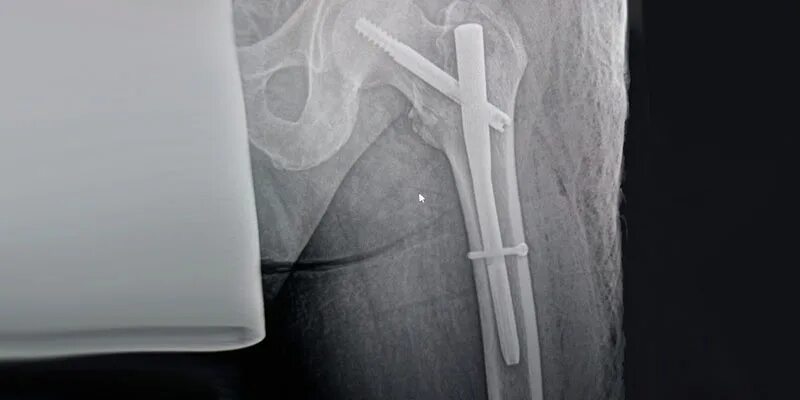

Остеосинтез чрезвертельного перелома